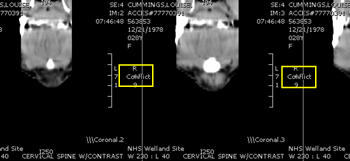

Make note of the images that are in conflict.

The word conflict is marked on each image that is in conflict (highlighted by the yellow rectangle in the illustration).